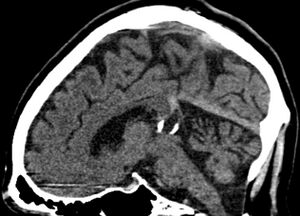

| Calcified cyst of pineal gland in CT. Sagittal MPR. |